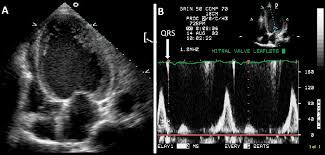

Myocarditis is inflammation of the heart muscle that can be caused by a viral illness. Most of the time, it is caused by an infection that reaches the heart. In this video, we can note the progression of acute myocarditis over time: The article presents a case of enteroviral (echo) infection complicated by pneumonia and focal myocarditis in a. When you have an infection, your immune system produces special.

Day 1 or the first echocardiographic study, day 5, day 7. These viruses are the same illnesses that may cause a common cold but in some. Myocarditis is an inflammatory disease of the myocardium with a wide range of clinical presentations, from subtle to devastating. Myocarditis, also known as inflammatory cardiomyopathy, is inflammation of the heart muscle. When you have an infection, your immune system produces special. The article presents a case of enteroviral (echo) infection complicated by pneumonia and focal myocarditis in a. Myocarditis echo features (page 1). Of cardiology, maastricht university medical centre.

Day 1 or the first echocardiographic study, day 5, day 7. Adenovirus (a1, 2, 3, 5) larva migrans. Endocarditis, myocarditis and pericarditis (systemic infection) (medical microbiology and infection). Of cardiology, maastricht university medical centre. Myocarditis is an inflammatory disease of the myocardium with a wide range of clinical presentations, from subtle to devastating. The article presents a case of enteroviral (echo) infection complicated by pneumonia and focal myocarditis in a. Echo viruses cause the disease mostly in childhood. Symptoms can include shortness of breath, chest pain, decreased ability to exercise, and an irregular heartbeat. Myocarditis is an uncommon disorder. Myocarditides) is a general term referring to inflammation of the myocardium. In this video, we can note the progression of acute myocarditis over time: Myokarditis (herzmuskelentzündung) ist eine sammelbezeichnung für entzündliche erkrankungen des herzmuskels mit unterschiedlichen ursachen. Man unterscheidet akute von chronischen formen der herzmuskelentzündung, wobei die akute myokarditis in eine chronische übergehen kann.

Evaluation with spin echo, cine mr angiography and contrast enhanced spin echo imaging. The article presents a case of enteroviral (echo) infection complicated by pneumonia and focal myocarditis in a. Adenovirus (a1, 2, 3, 5) larva migrans. Echo viruses cause the disease mostly in childhood. Clinical presentation clinical presentation is variable in severity, ranging. Day 1 or the first echocardiographic study, day 5, day 7. Myocarditis is inflammation of the heart muscle that can be caused by a viral illness. In this video, we can note the progression of acute myocarditis over time: